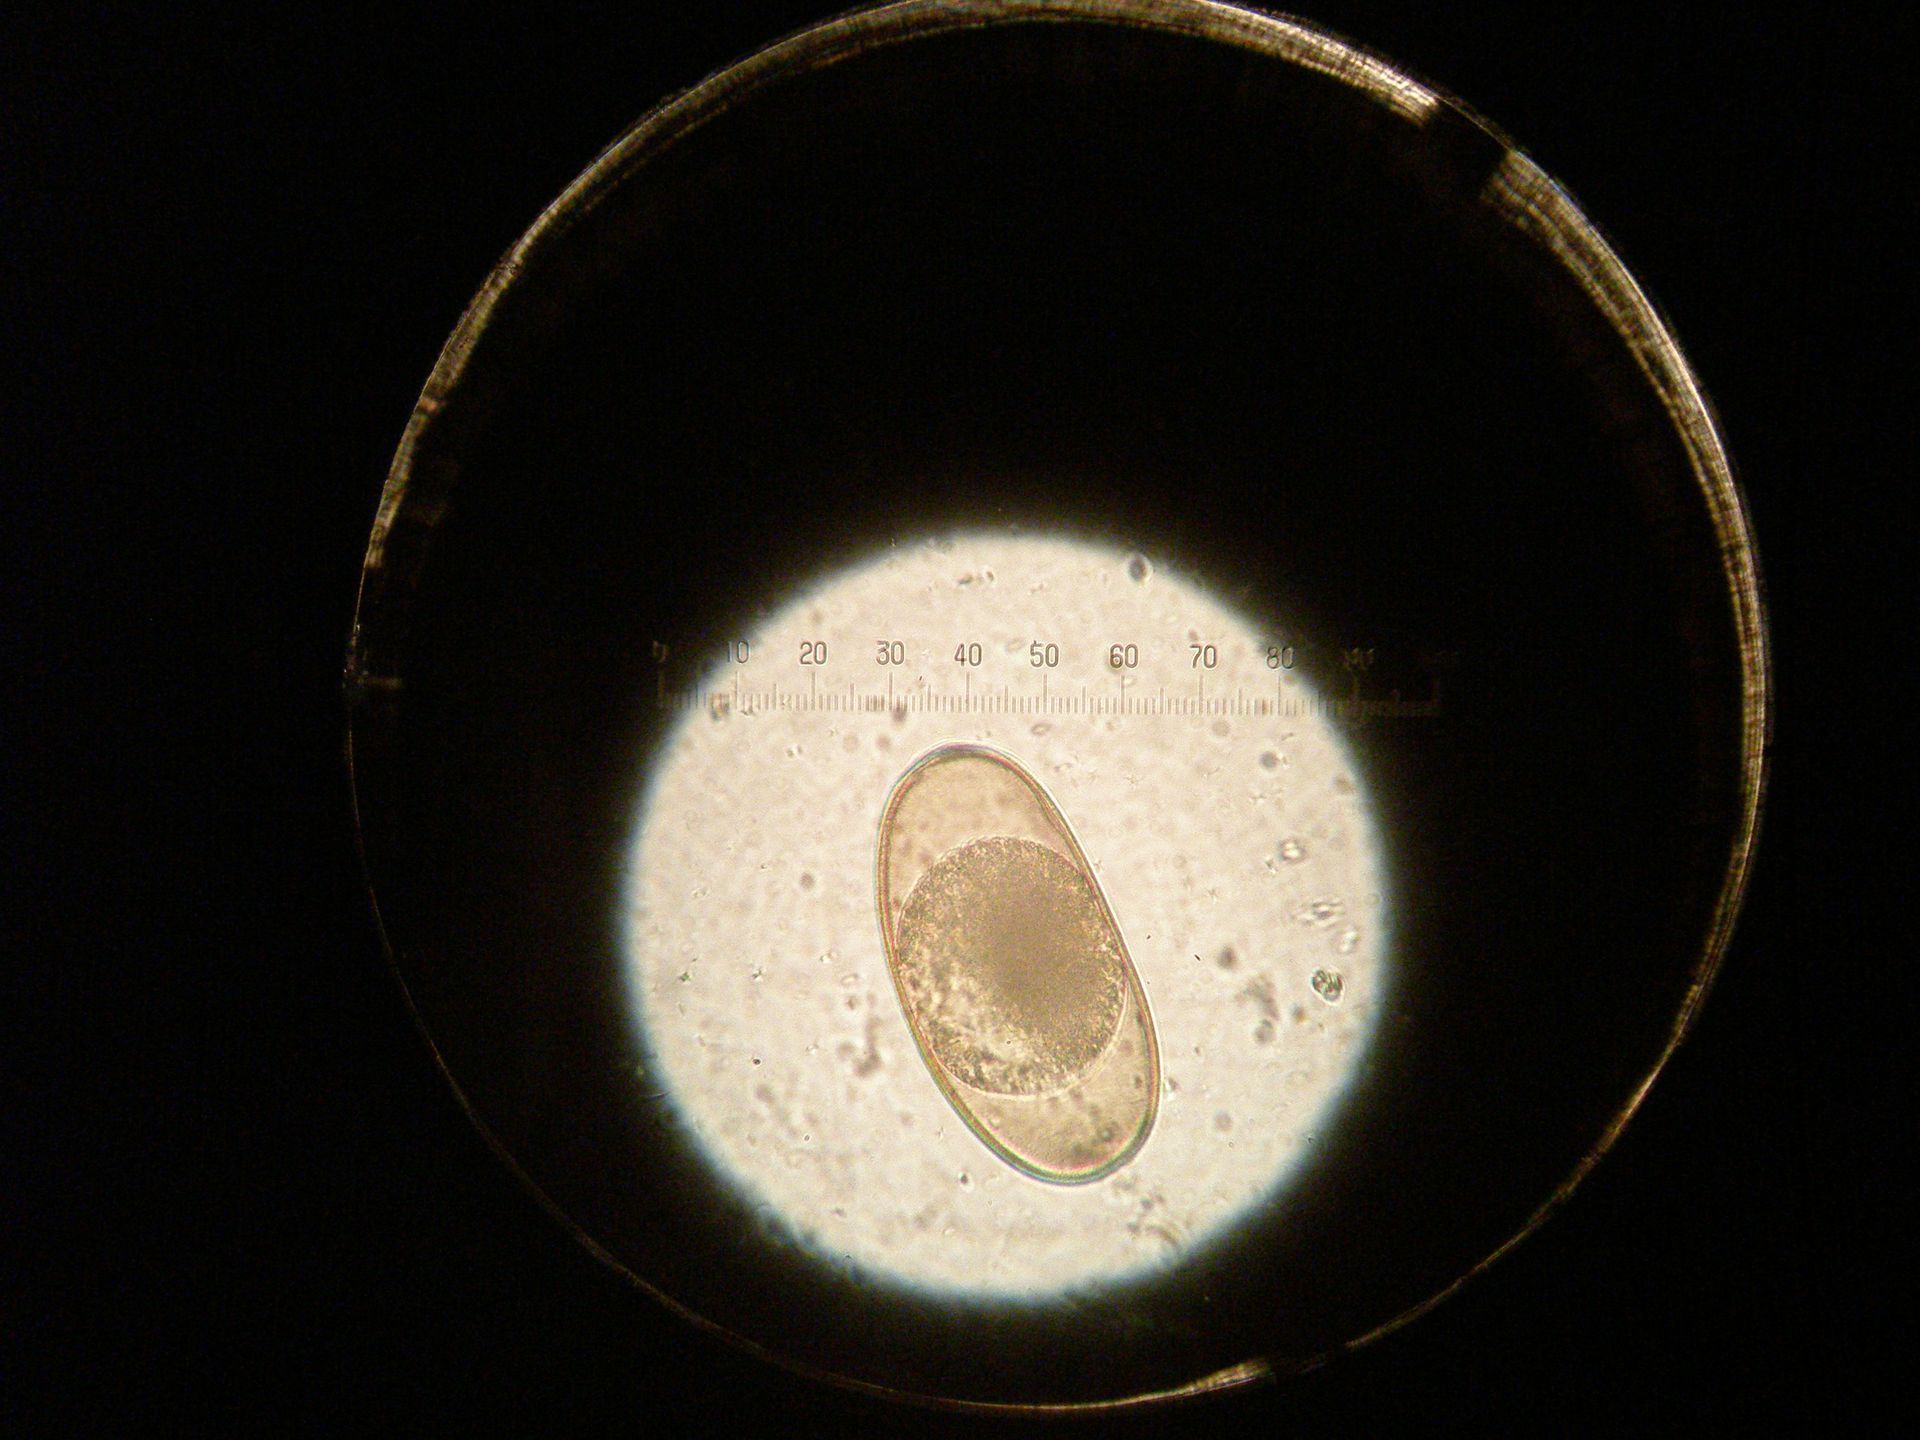

Parasites digestifs

Les parasites digestifs font partie de la flore digestive de certains reptiles comme chez les tortues ou ils participent à la digestion des végétaux. Mais dans certains cas, leur prolifération provoque des pathologies sévères et il convient alors de réguler par l'administration d'anti-parasitaire.

Les parasites sont nombreux : nématodes, trematodes, flagellés et nécessitent des traitements différents pour chacun d'eux. La réalisation d'examen coproscopique quand elle est possible est nécessaire pour s'assurer de l'efficacité du traitement.